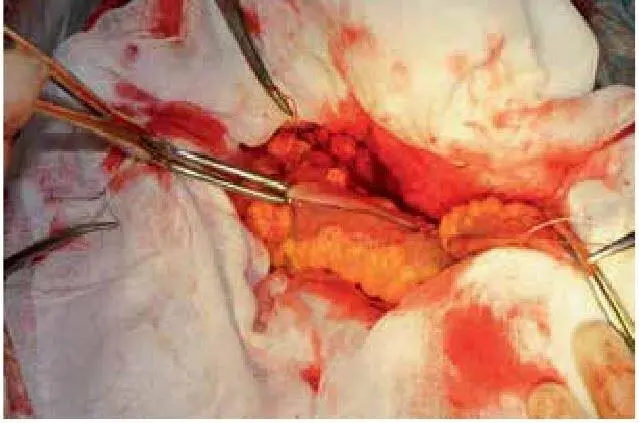

Рис. 80. Заведение игл с трубочками в просвет двух отделов кишки

Рис. 81. Бранши устройства максимально сближены, фиксированны

Рис. 82. Три лигатуры удерживают трубочки, ссдавливающие ткани стенки кишки; одна лигатура – для удержания трубочек в просвете кишки

Результаты.Группу исследования составили 25 пациентов в возрасте от 39 до 78 лет. Все 25 пациентов оперированы в экстренном порядке по поводу кишечной непроходимости, перитонита различной этиологии. Все анастомозы раскрылись.

1. Аппаратная методика формирования ОМКА обусловило облигатное раскрытие всех сформированных анастомозов путем усиленной, равномерной компрессии стенки кишки;

2. Использование аппаратного способа формирования ОМК позволило избежать сложной повторной внутрибрюшинной реконструктивно-восстановительной операции;

3. Разработанный аппаратный способ формирования отсроченного межкишечного компрессионный анастомоза безопасен, и значительно сокращает время формирования анастомоза.